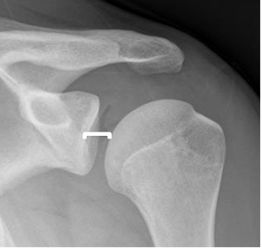

Se diagnostica cuando la cabeza humeral, se localiza por debajo de la apófisis coracoides. (11). (Fig 45 A y B, 46 y 47).

Fig 45 A. Luxación anterior.

Rx AP. Cabeza humeral por debajo de la coracoides, por luxación anterior.